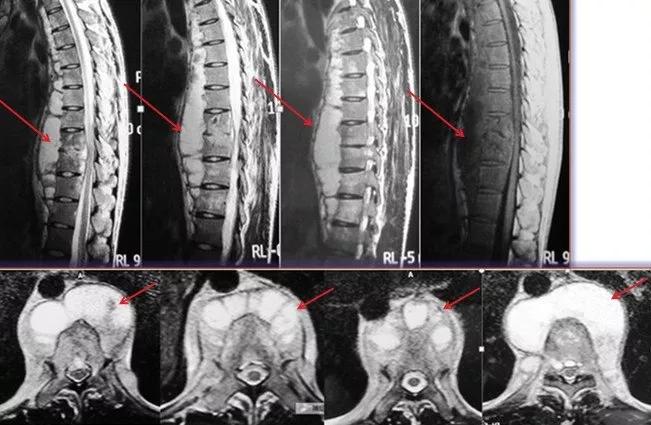

2、这是一个成年男性患者,因轻微背痛就诊。影像检查发现脊柱结核。从核磁看(红色箭头示)胸椎多节段椎前脓肿,但椎体和椎间隙狭没有明显炎性病变或破坏。

这属于“骨膜下型”脊柱结核,可以采取保守治疗。制定抗结核治疗方案后,定期随诊复查。

抗结核治疗六个月后,脓肿吸收不明显(红色箭头示)。

患者背痛仍不明显,椎体和椎间盘也无破坏。继续保守治疗,但调整抗结核药物,重新组合药物方案。用药一年后,脓肿完全吸收(红色箭头示)。病灶愈合。